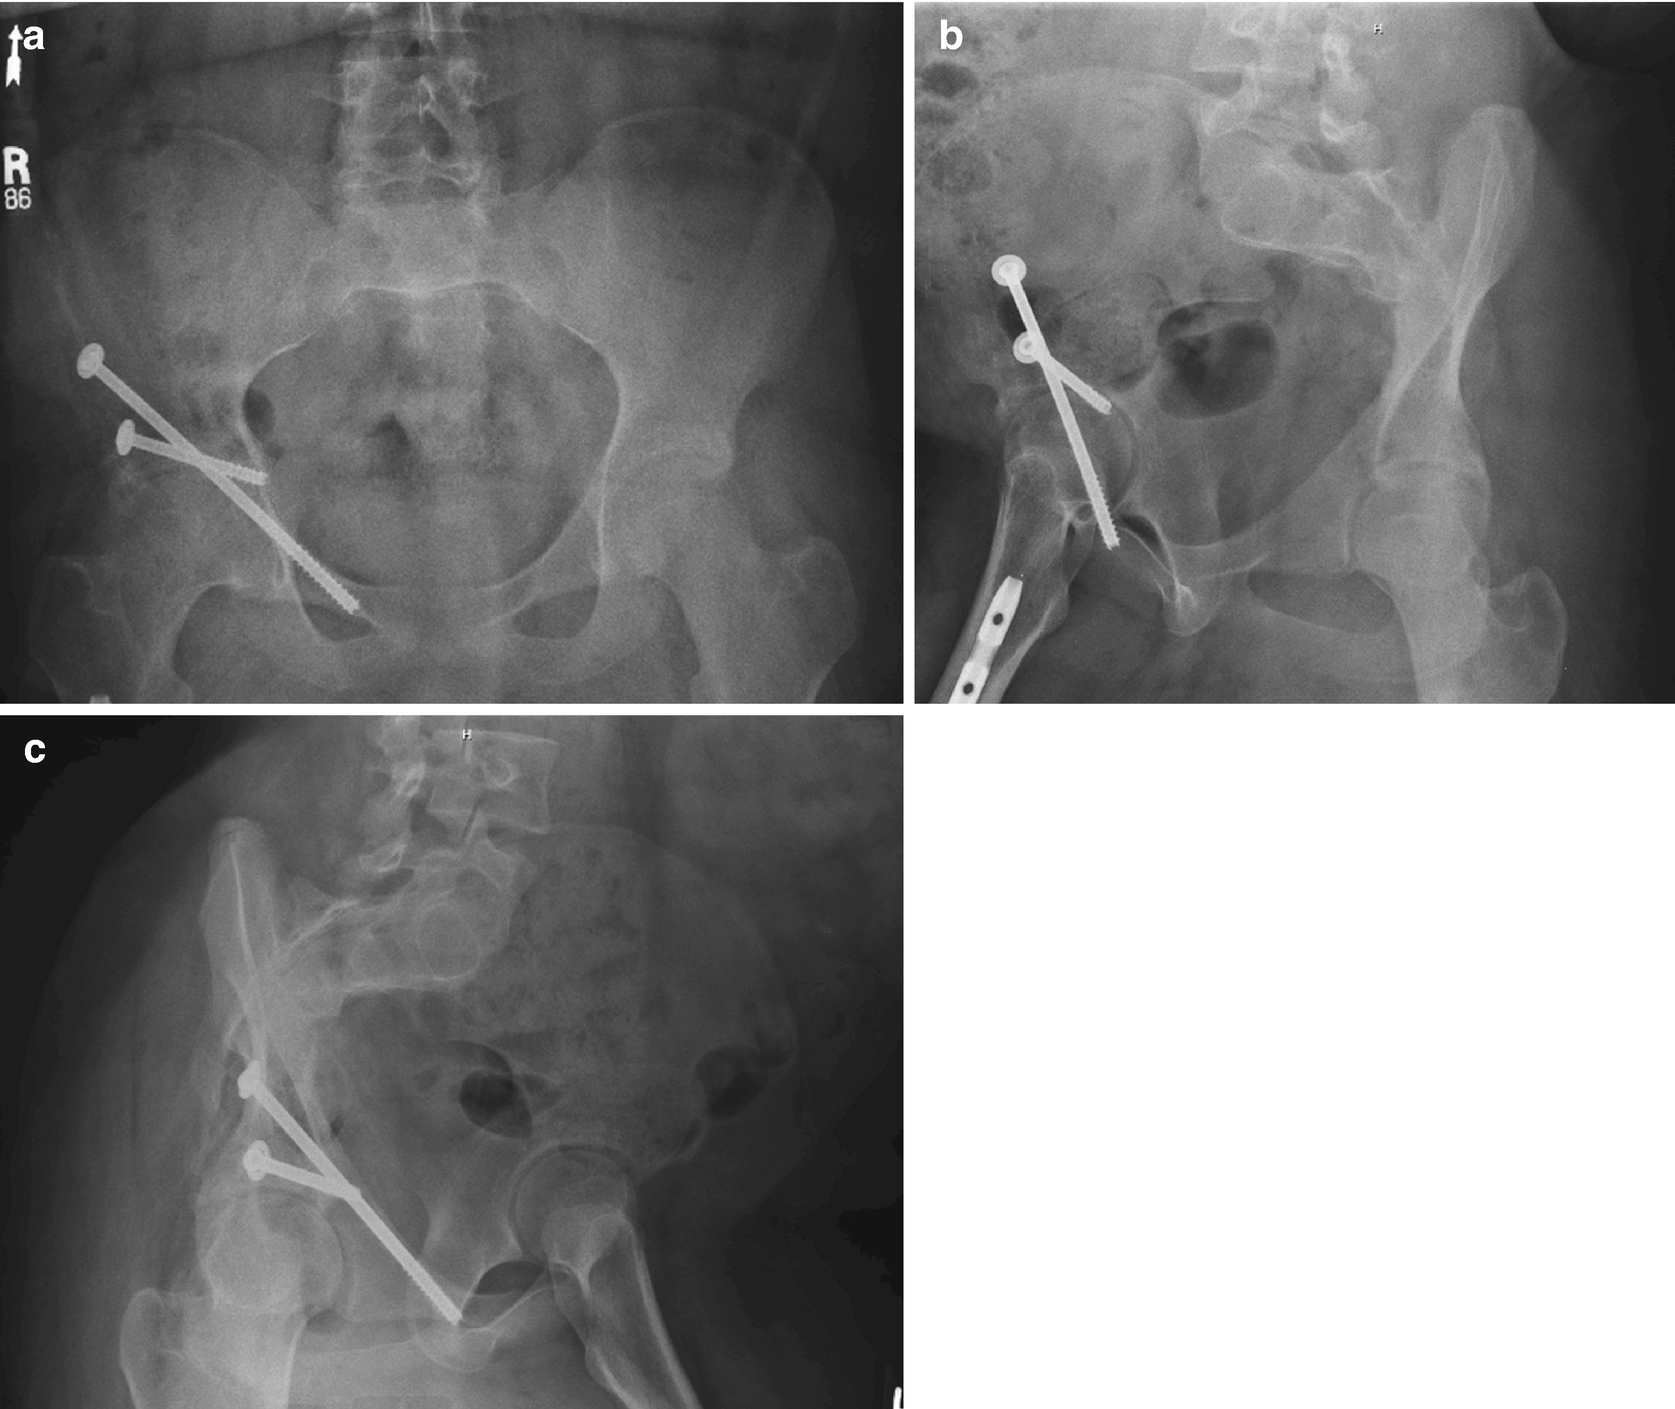

Modified Stoppa Approach For Pelvic And Acetabular Fracture Treatment

Acetabulum Two Column Fractures Springerlink

Optimizing The Anatomic Reduction Of Complex Acetabular Fractures A Technical Enhancement To The Modified Stoppa Approach